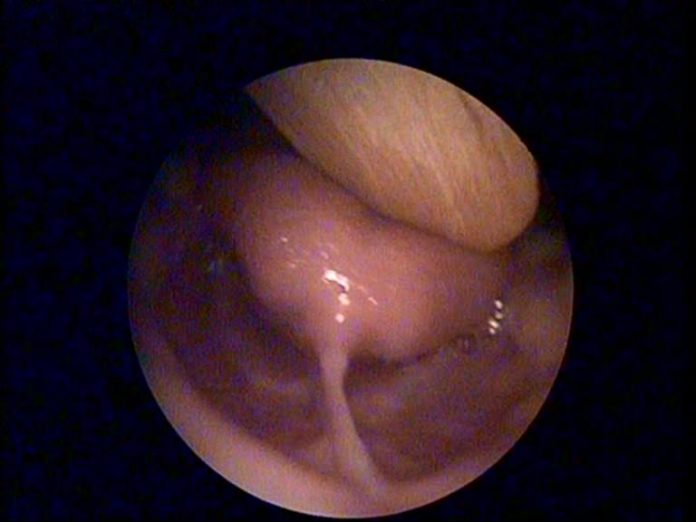

Bu videoda; Ağız boşluğu nasıl şekillenir, dil bağı kendiliğinden yırtılır mı ? dil bağı tedavisi yaşı … konularını izleyebilirsiniz.